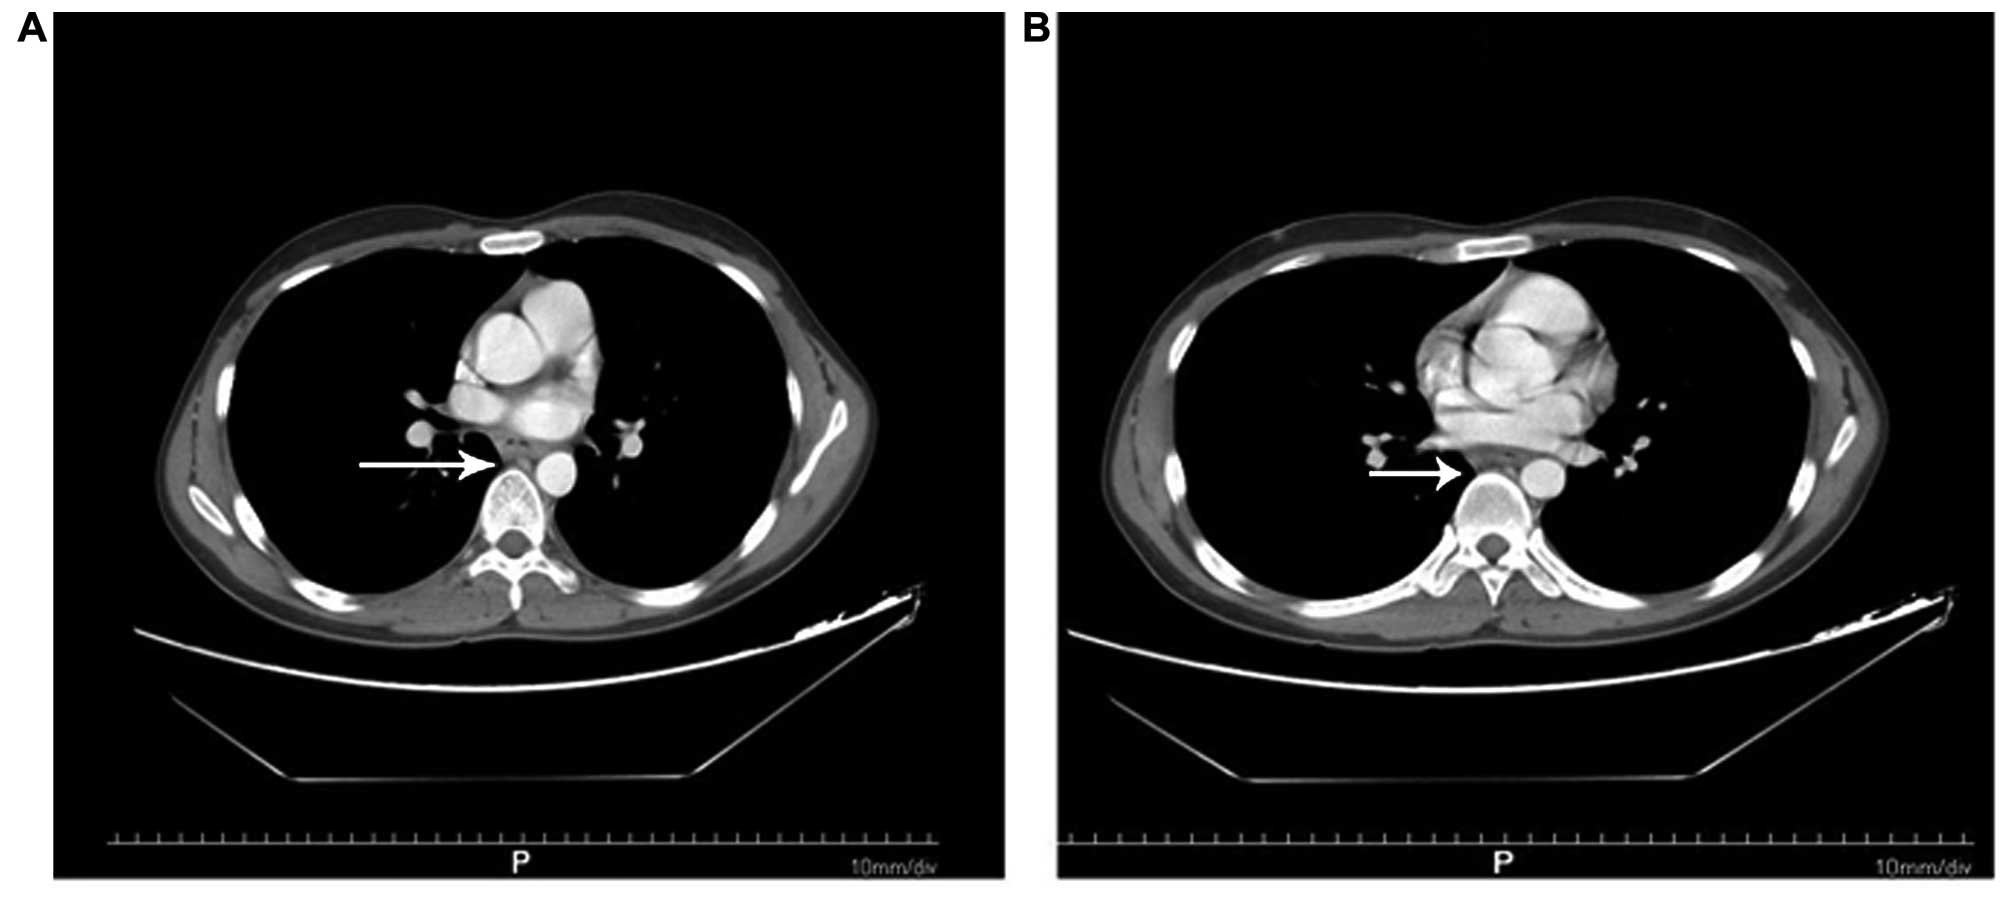

A 21-year-old man, who had been diagnosed in 2011 with nasal NK/T-cell lymphoma, was admitted to the Department of Oncology at Tai-He Hospital (Hubei, China). The patient was treated with 4 cycles of cyclophosphamide, vincristine, daunorubicin and dexamethasone (CHOP regimen), followed by local radiotherapy with 56 Gy in 26 fractions (2.15 Gy/fraction) of gross tumor volume. The patient remained in remission until April, 2014, when he was admitted with a 2-month history of discontinuous fever peaking to 39°C without an obvious cause, and difficulty in swallowing. The patient underwent an emergent esophagogastroduodenoscopy, which revealed an irregular mucosal elevation at a distance of 30–36 cm from the incisors. The mucosal surface was eroded and mildly indurated. A computed tomography scan revealed a mild thickening of the wall of the lower esophagus (Fig. 1). The barium swallow indicated slow passing of the barium through the lower esophagus (equivalent to the level of the thoracic vertebrae 7–9), with esophageal wall stiffness, mildly limited expansion and mucosal damage; the length of lesion was ~8.1 cm (Fig. 2). The patient reported no symptoms of cough, expectoration, hemoptysis or abdominal pain.